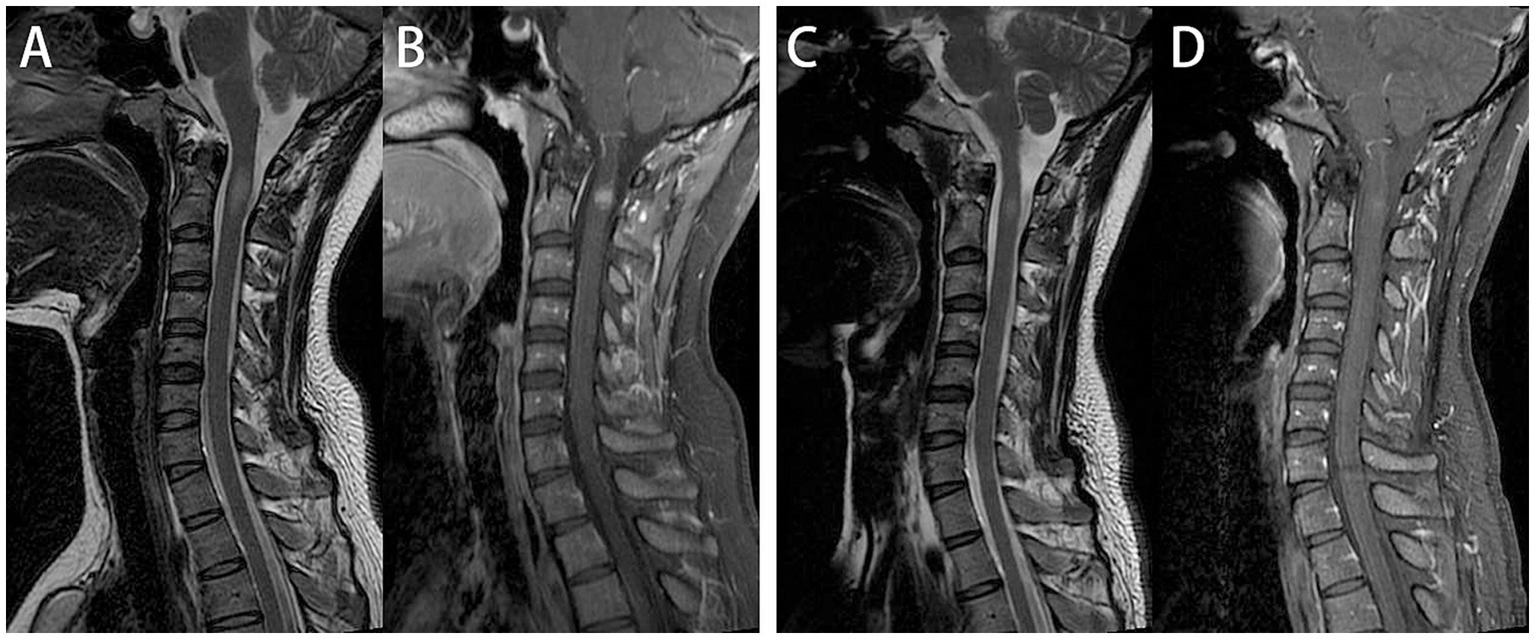

After admission, enhanced MRI of the brain and cervical spinal cord revealed multiple abnormal signals in the intracranial region and cervical spinal cord, with nodular, patchy, or irregular enhancement (Figures 1A–E,a–e, 2A,B). The central vein sign refers to the enhanced venous vascular shadow observed at the center of the lesion, surrounded by abnormal lesional tissue, which was detected on T1-weighted enhanced sequences (Figures 1b–d). Thoracic spinal cord MRI showed no significant abnormalities. Chest CT indicated bilateral minimal pleural effusion.

Figure 2

Cervical spinal cord plain and enhanced magnetic resonance imaging (MRI). On admission, cervical spine MRI demonstrated intramedullary abnormal signals at the C2 level, with nodular uniform enhancement (A,B). One month later, follow-up cervical spine MRI showed that One month later, follow-up cervical spine MRI showed that a significant reduction in both the extent of the T2WI hyperintense and enhancing lesions (C,D).

The patient was initiated on a therapeutic regimen consisting of oral trimethoprim-sulfamethoxazole (TMP-SMX) 1.44 g every 8 h, intravenous amikacin 0.8 g once daily, and intravenous imipenem-cilastatin sodium 0.5 g every 6 h. Notable gastrointestinal toxicities, including anorexia, nausea, and emesis, necessitated the addition of mosapride, pantoprazole, and vitamin B6, with subsequent resolution of these symptoms. Imipenem-cilastatin sodium was discontinued at 3 weeks, followed by amikacin discontinuation at 6 weeks. One month after therapy initiation, lumbar puncture revealed normal CSF pressure (170 mmH2O), mild leukocytosis at 15 × 106/L (monocyte-predominant), and normal protein and glucose levels. Repeat CSF mNGS yielded negative results, whereas serum MOG-IgG remained persistently positive with stable titers. Serial cranial and cervical spinal MRI demonstrated reduction in lesion size and marked attenuation or resolution of enhancement (Figures 1F–J,f,g, 2C,D). At the 6-week treatment milestone, the regimen was transitioned to oral TMP-SMX in combination with minocycline 100 mg twice daily, with recommendations for continuation for a minimum of 12 months. Complete clinical remission was achieved 2 months following treatment initiation.